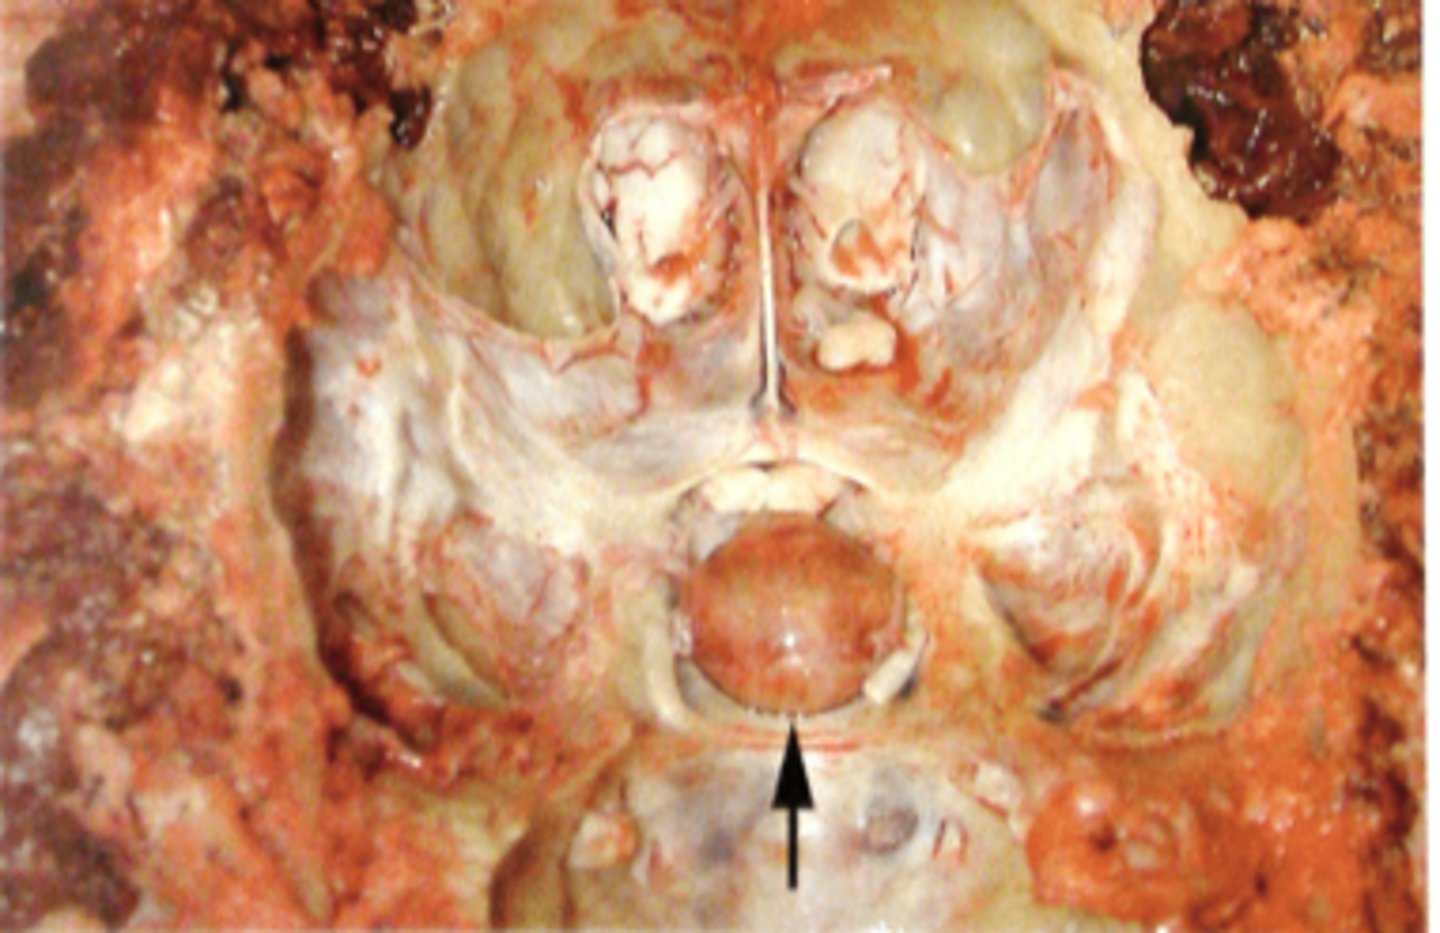

kronisk, fokal apostematøs osteomyelitis mellem S og O med opbrud til hypofysen. Kronisk meningitis (pil hovede). Purulent encephalitis og pyocephali (pil)

Hoved fra okse. Patoanatomisk diagnose?